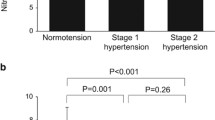

Coronary minimum vascular resistance (C-Rmin) decreased by 22±8% (group 1, P=0.02) and 24±4% (group 2, P<0.001) during the 6 months of additional treatment (group 1 vs 2: P=0.80, Figure 2). CFR increased by 23±3% (group 1, P<0.001) and 17±3% (group 2, P<0.001; group 1 vs 2: P=0.16). This was caused by a combination of decreased resting coronary flow velocity and increased flow velocity during adenosine-induced hyperaemia. No significant change was observed in forearm minimum vascular resistance; 6.5±6.3% (group 1, P=0.79) vs −2.0±4.8% (group 2, P=0.38; group 1 vs 2: P=0.30), see Figure 2, Table 2b.